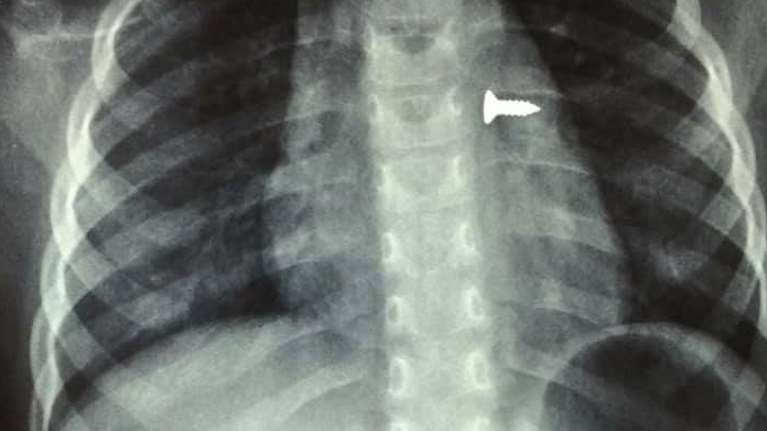

Σοκ στην Κρήτη: 3χρονη κατάπιε βίδα και κατέληξε στον πνεύμονά της [εικόνες]

Σοκ προκαλούν οι ακτινογραφίες ενός 3χρονου κοριτσιού, που κατάπιε βίδα, η οποία κατέληξε στον αριστερό του πνεύμονα.